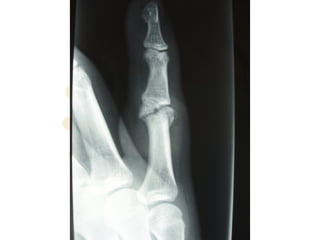

ď‚§ Type III (fracture-dislocation):

disruption at the volar base of

MP where VP is inserted; stable

vs unstable injuries

Dorsal PIPJ Dislocations

ď‚§ Stable Type III:

ď‚§ fracture < 40% of volar

base MP; significant

portion of col. ligs. still

attached; possible

congruous reduction

ď‚§ Unstable Type III:

ď‚§ fracture > 40% of volar

base MP; little or no col.

ligs. attached; congruous

reduction unlikely;

depressed volar articular

defect